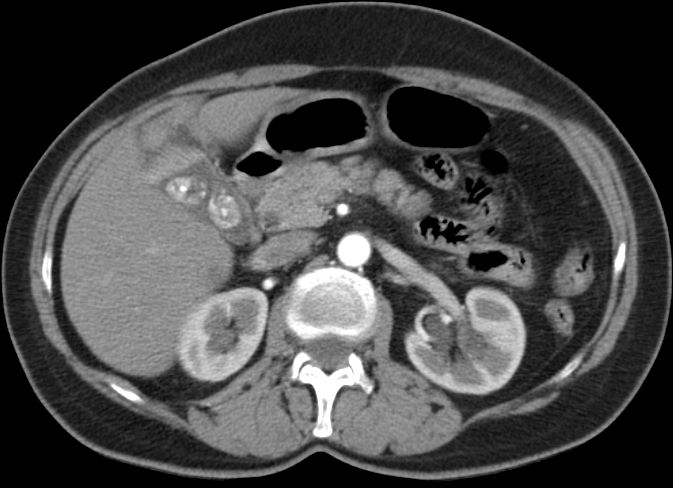

Beispiel: CT eines Funduskarzinoms in einer

Stein-Blase ![]() |

![]() |